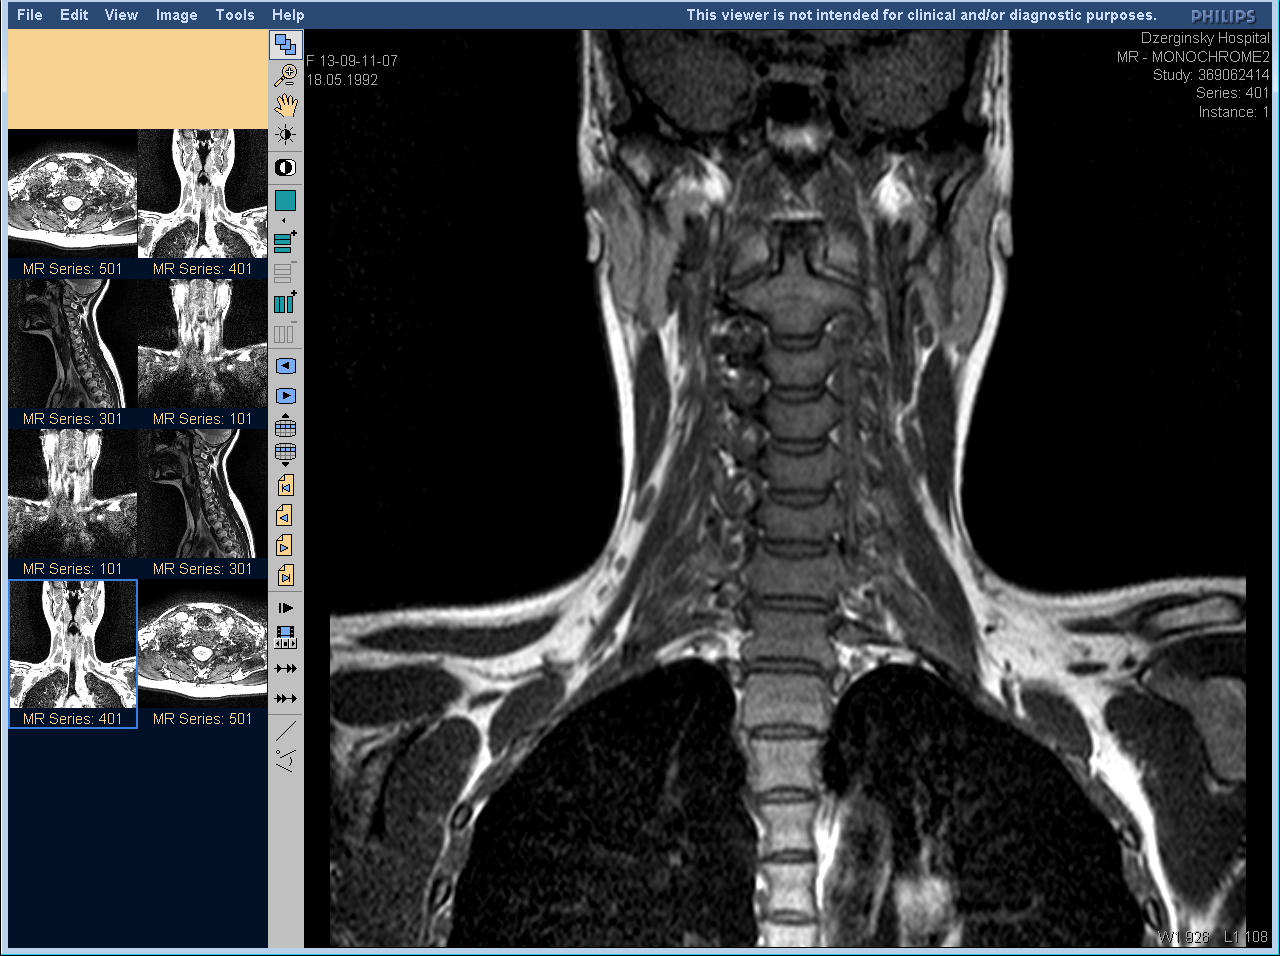

Компьютерная и магнитно-резонансная томография дают более точный результат, но при этом имеют ряд противопоказаний, так что назначают их не всем пациентам.

МРТ шейного отдела позвоночника и сосудов шеи